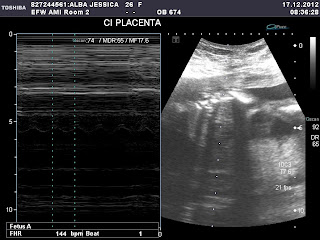

Hoy fuimos los tres para tomarte más fotitos. ¡Ay pero que te dejas ver! No te pudieron tomar buenas fotos de tus órganos porque no te estabas en paz haha so iremos otra vez el jueves para mas fotos. A pesar de que nos gusta verte seguido te tienes que dejar ver para que te revisen bien. Aquí está la foto con tu eco de esta vez.

Aquí está tu cabecita a 20 semanas…